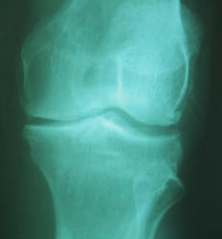

SJ is a 60-year-old male with bone on bone osteoarthritis of the left

knee. An X-ray showed arthritis of the knee (X-ray on the left). Patient started receiving

treatments at The Center For Regenerative Medicine. Today he is feeling better (X-ray

on the right).